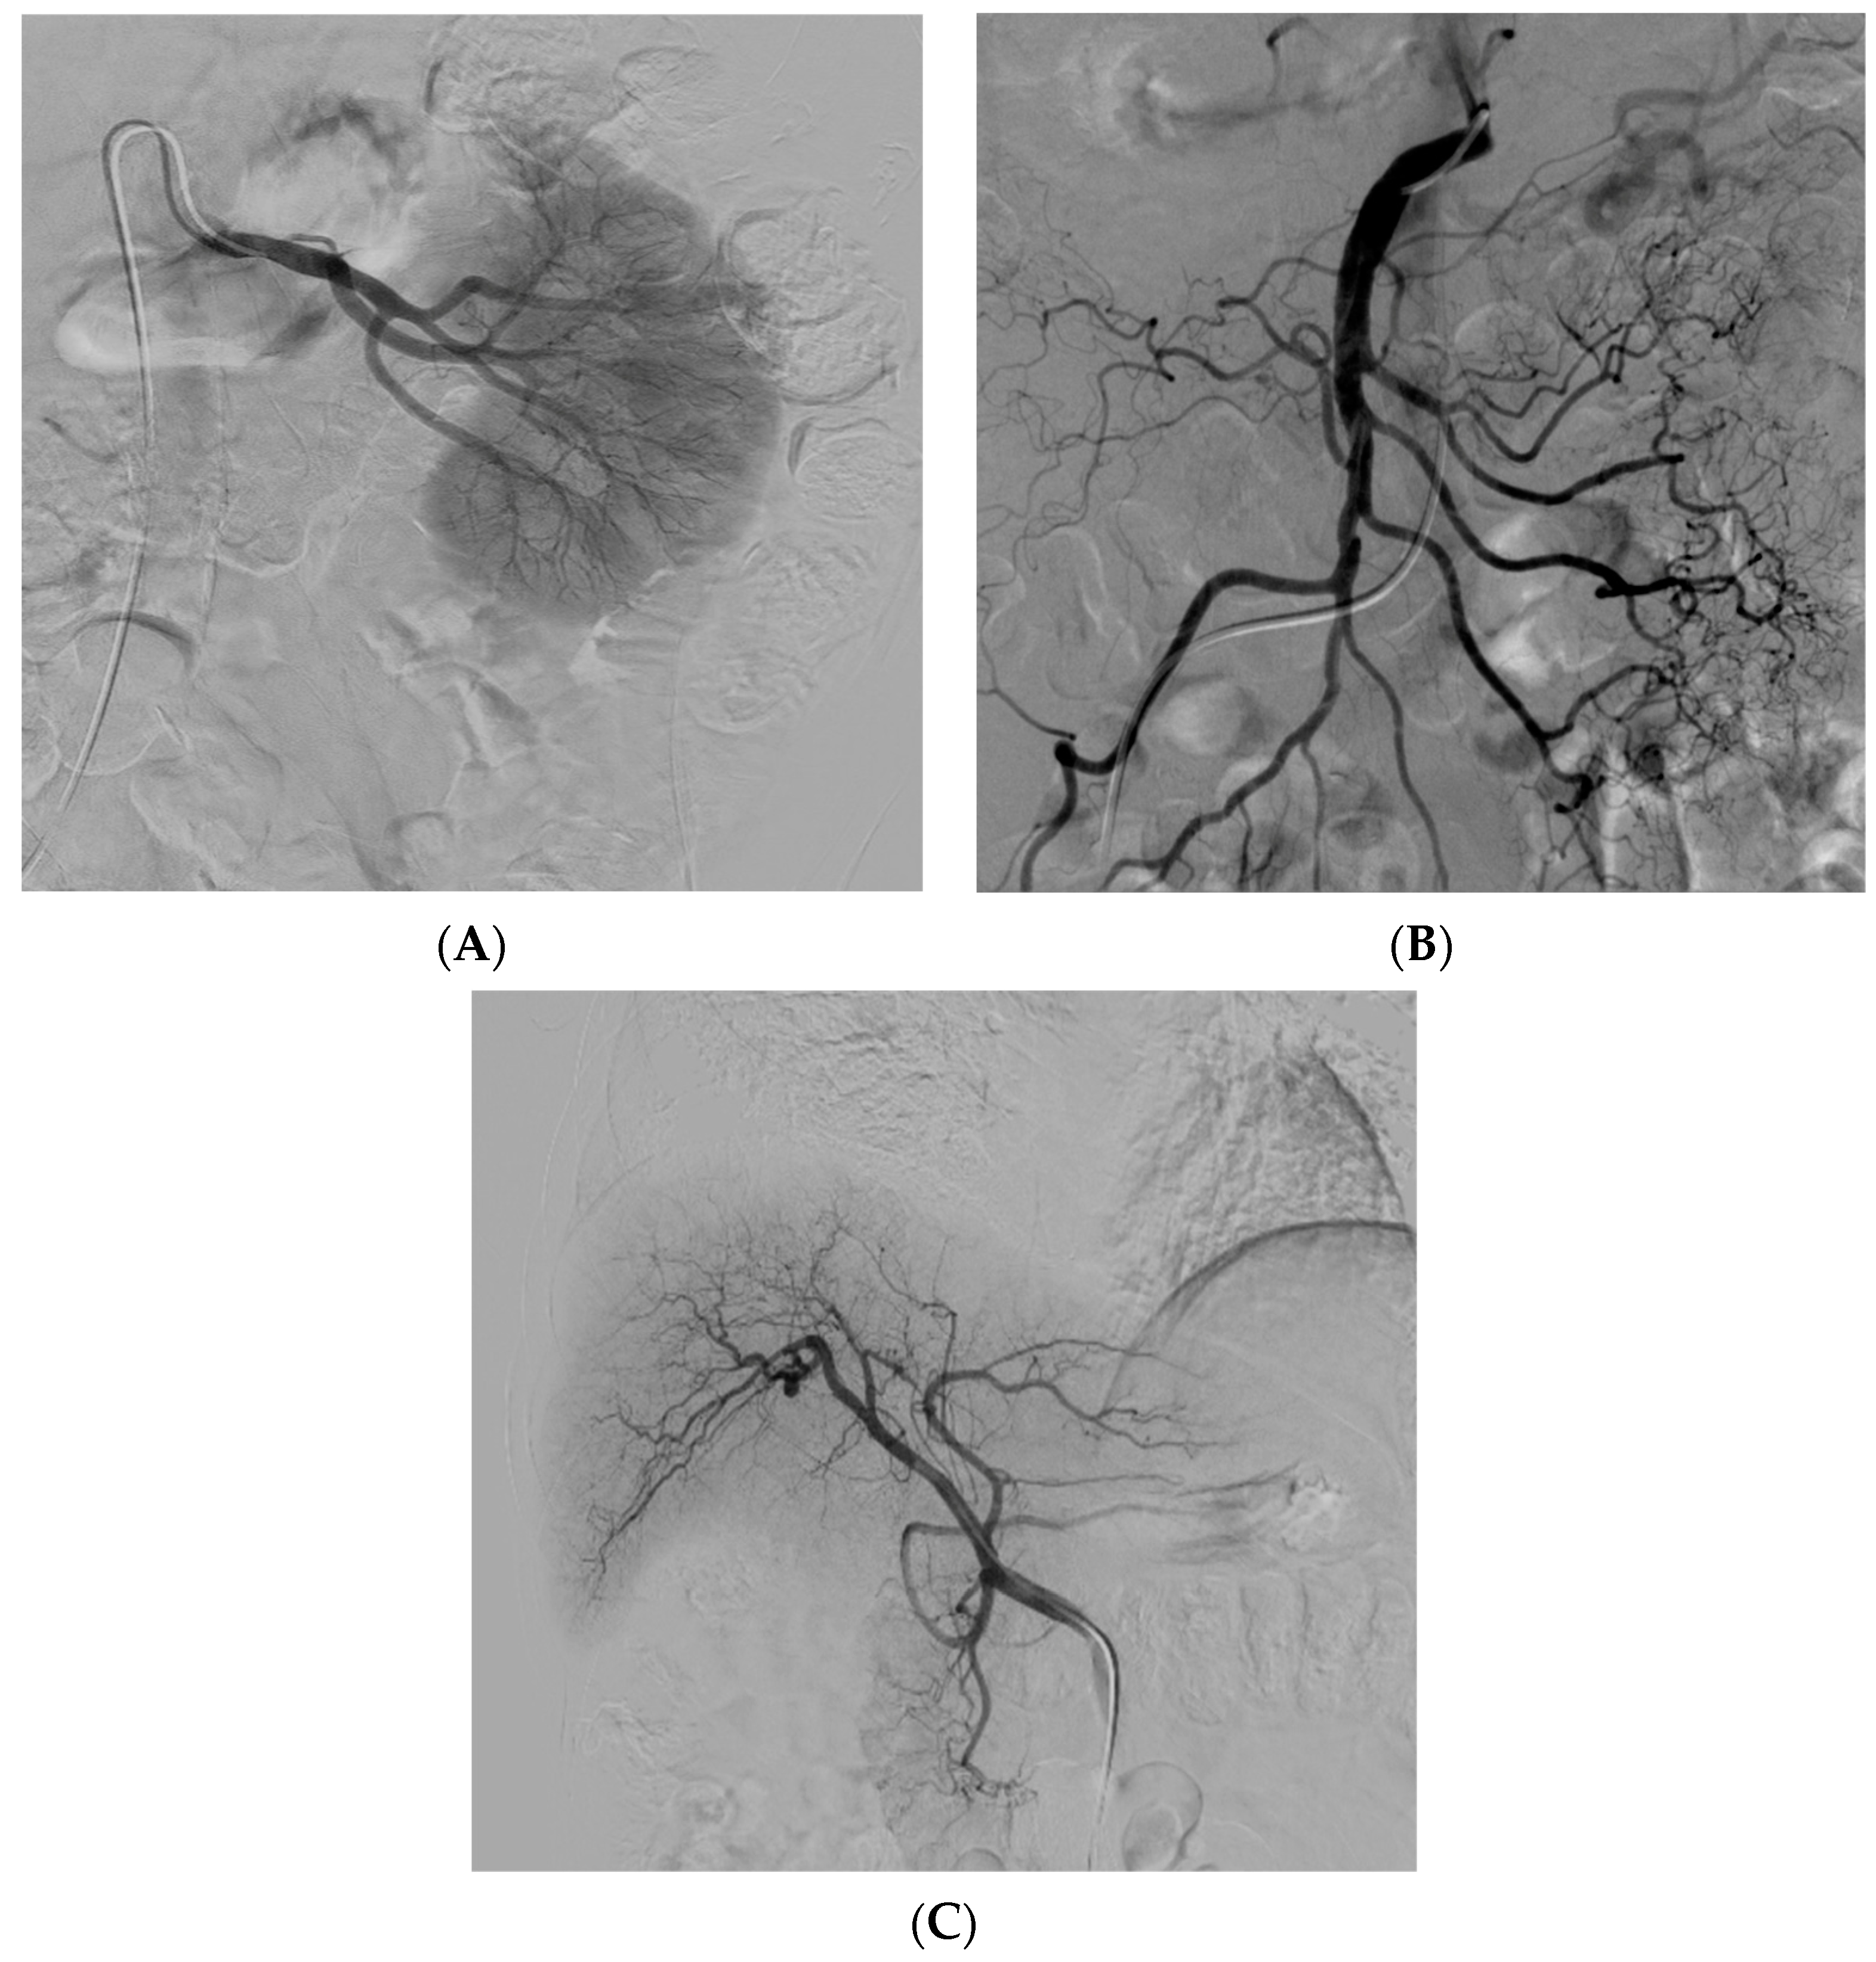

3.5. Peripheral Arterial Disease

- Mao, Q.; Wang, W.; Xu, T.; Zhang, S.; Xiao, L.; Chen, D.; Jin, H.; Tong, P. Combination treatment of biomechanical support and targeted intra-arterial infusion of peripheral blood stem cells mobilized by granulocyte-colony stimulating factor for the osteonecrosis of the femoral head: A randomized controlled clinical trial. J. Bone Miner. Res. 2015, 30, 647–656. [Google Scholar] [CrossRef] [PubMed]

- Pan, J.; Ding, Q.; Lv, S.; Xia, B.; Jin, H.; Chen, D.; Xiao, L.; Tong, P. Prognosis after autologous peripheral blood stem cell transplantation for osteonecrosis of the femoral head in the pre-collapse stage: A retrospective cohort study. Stem Cell Res. Ther. 2020, 11, 83. [Google Scholar] [CrossRef] [PubMed]

- Klepanec, A.; Mistrik, M.; Altaner, C.; Valachovicova, M.; Olejarova, I.; Slysko, R.; Balazs, T.; Urlandova, T.; Hladikova, D.; Liska, B.; et al. No difference in intra-arterial and intramuscular delivery of autologous bone marrow cells in patients with advanced critical limb ischemia. Cell Transplant. 2012, 21, 1909–1918. [Google Scholar] [CrossRef]